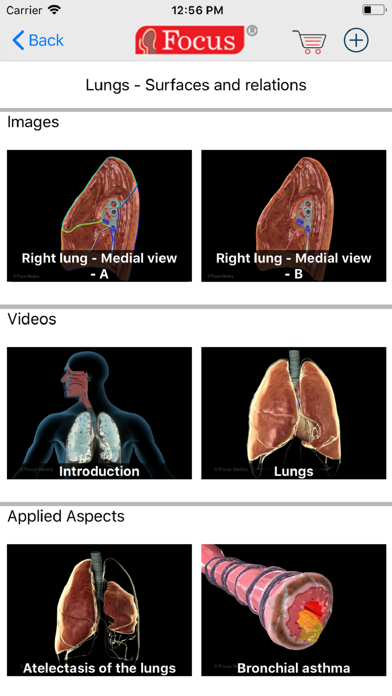

- The most comprehensive Atlas with an exhaustive array of plates

- Includes 3D animation videos of important applied aspects with clinical perspectives

- Includes Interactive images with detailed description for each label, enabled with user-paced on/off feature and zoom-in/out options

- Extensive information accessible through valuable visual tools using 3D animations accompanied by audio and interactive images